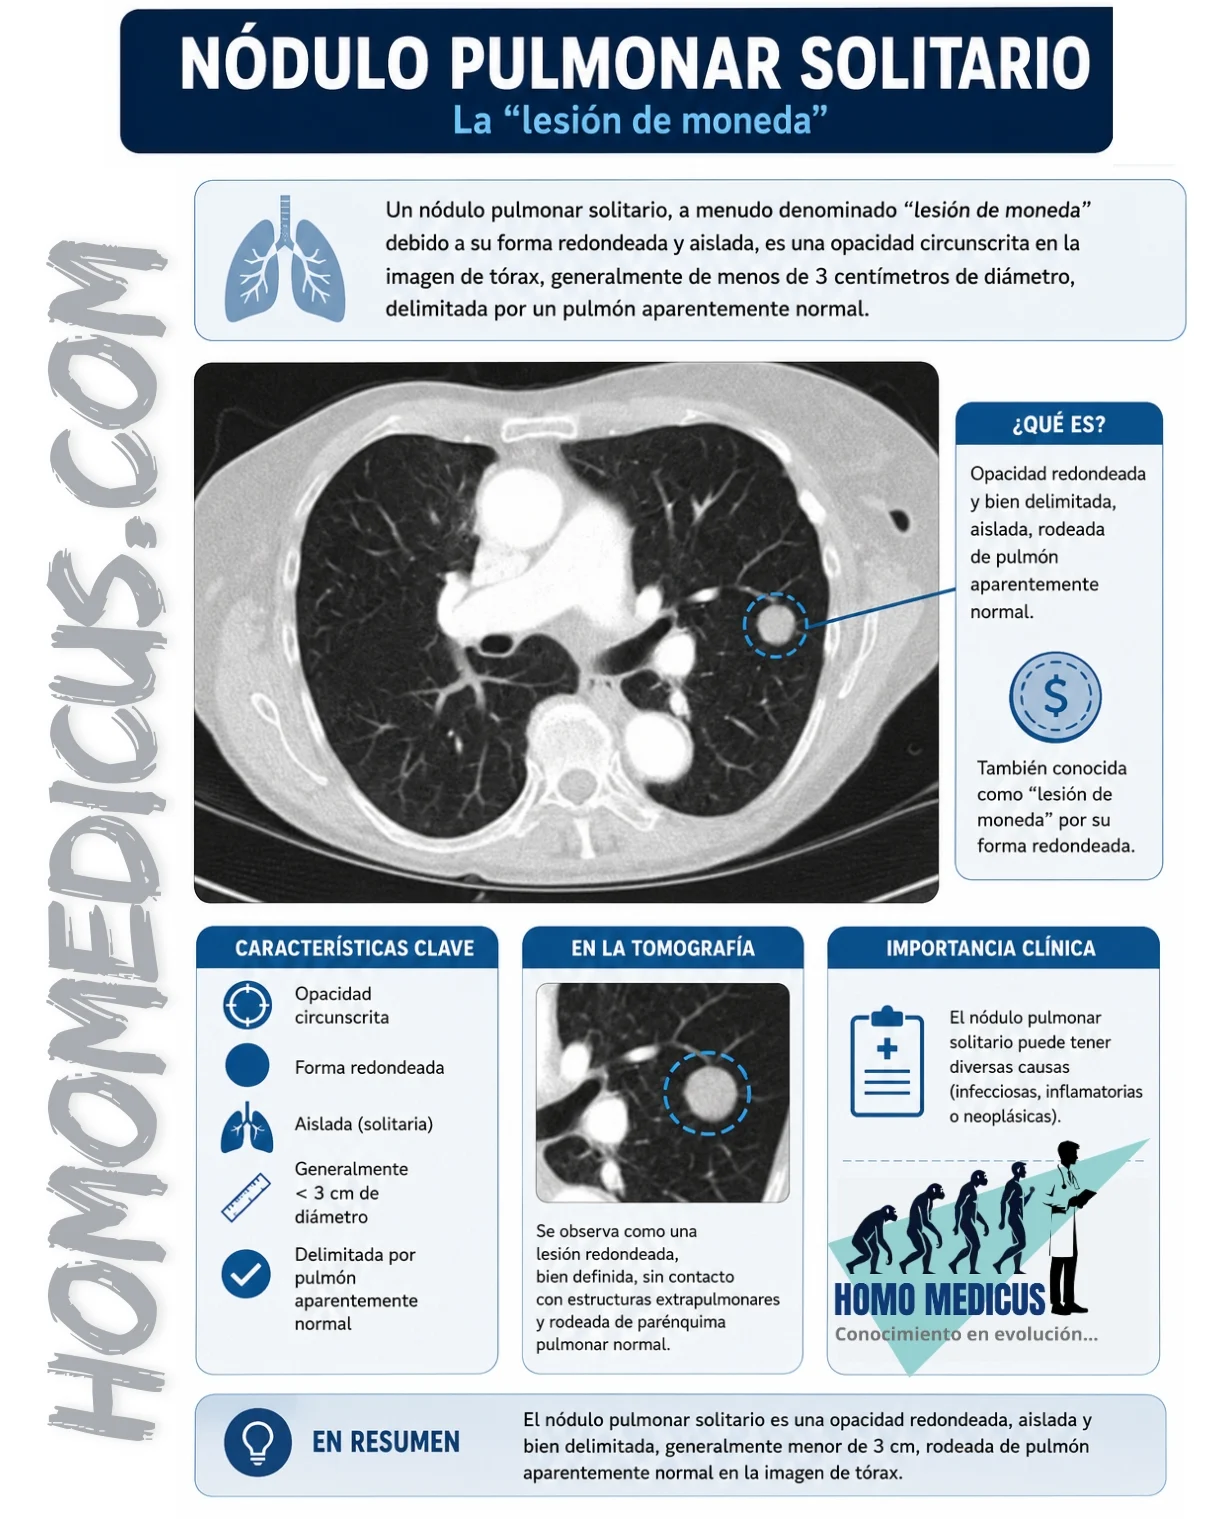

Un nódulo pulmonar solitario, a menudo denominado “lesión de moneda” debido a su forma redondeada y aislada, es una opacidad circunscrita en la imagen de tórax, generalmente de menos de 3 centímetros de diámetro, delimitada por un pulmón aparentemente normal. Su identificación en imágenes radiográficas o en tomografías computarizadas es un hallazgo importante que requiere una evaluación cuidadosa debido a la diversidad de su posible etiología.

Estos nódulos pueden ser clasificados en sólidos, subsólidos con vidrio esmerilado o de consistencia mixta. La mayoría de ellos son asintomáticos y se descubren incidentalmente durante estudios de imagen realizados por otras razones. Su aspecto redondeado y aislado en el contexto de un pulmón normal sugiere que están bien delimitados y no asociados con otras anomalías pulmonares.

La evaluación de un nódulo pulmonar solitario para determinar su probabilidad de malignidad se basa en una combinación de datos clínicos y características radiográficas. La tomografía computarizada (TC) juega un papel crucial en esta evaluación debido a su capacidad para proporcionar una visión detallada del nódulo y de su entorno.

Además de la evaluación temporal, las características radiográficas del nódulo son fundamentales. El tamaño del nódulo está estrechamente relacionado con el riesgo de malignidad. Estudios han demostrado que la tasa de malignidad varía significativamente con el tamaño del nódulo, siendo mucho más alta en nódulos grandes. Para nódulos de 2 a 5 mm, la tasa de malignidad es del 1%. En nódulos de 6 a 10 mm, la tasa aumenta al 24%. Nódulos de 11 a 20 mm presentan una tasa de malignidad del 33%, mientras que nódulos de 21 a 45 mm tienen una tasa de malignidad del 80%. Este incremento en la tasa de malignidad con el tamaño sugiere que los nódulos más grandes tienen una mayor probabilidad de ser malignos.

Las características de los bordes del nódulo también son indicativas. Un borde liso y bien definido es generalmente asociado con procesos benignos, mientras que los márgenes mal definidos o lobulares sugieren una mayor probabilidad de malignidad. La presencia de márgenes espiculados y un halo periférico, observados a través de la TC de alta resolución, están altamente correlacionados con malignidad. Estos hallazgos reflejan una posible invasión del tejido circundante, un signo común de cáncer.